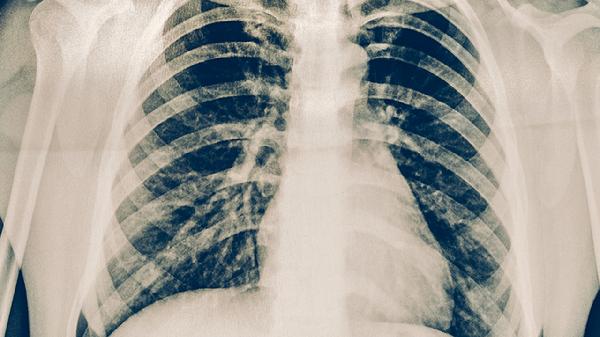

睡眠剝奪會導致皮質(zhì)醇晝夜分泌紊亂,持續(xù)高水平糖皮質(zhì)激素可能抑制T細胞增殖。褪黑素分泌減少可能削弱抗氧化防御系統(tǒng),增加肺部組織對結(jié)核桿菌的易感性。這種情況可能需進行胸部CT檢查,排除肺門淋巴結(jié)腫大等病變。

保持每天7-8小時高質(zhì)量睡眠有助于維持免疫穩(wěn)態(tài),夜間工作人群應保證白天睡眠環(huán)境黑暗安靜。飲食注意補充優(yōu)質(zhì)蛋白和維生素A/C/D,適量食用牛奶、雞蛋、西藍花等食物。出現(xiàn)持續(xù)咳嗽超過2周、午后低熱、痰中帶血等癥狀時,應及時到結(jié)核病防治機構(gòu)進行痰涂片檢查和胸部影像學評估。確診患者需嚴格遵醫(yī)囑完成6-9個月規(guī)范抗結(jié)核治療,常用藥物包括異煙肼片、利福平膠囊、吡嗪酰胺片等,治療期間須定期監(jiān)測肝功能。